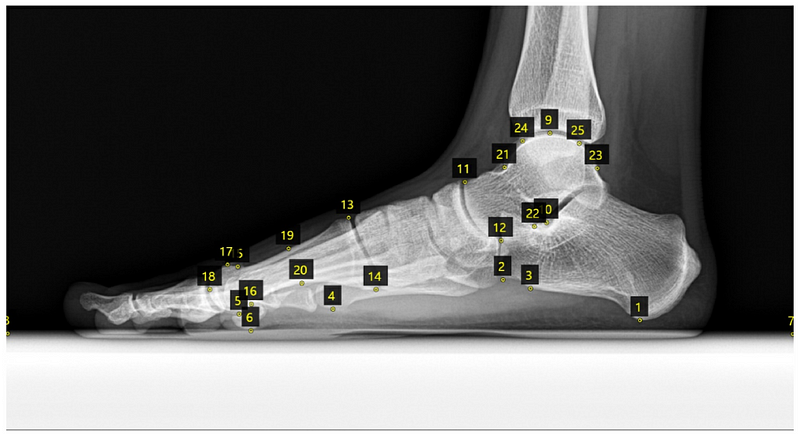

25개의 해부학적 랜드마크를 정의하였습니다:

1) 종골 관련(3개): 하연, 결절, 전하방 모서리

2) 종골 참조점 관련(5개): 5번 중족골 두부 하연, 1번 중족골 두부 하연, 종자골 하연, 후방 지면, 전방 지면

3) 거골 관련(9개): 거골 돔 상연, 외측 돌기, 거골 두부 전상방 모서리, 거골 두부 전하방 모서리 등

4) 첫 중족골 관련(8개): 기저부 상후방 모서리, 기저부 하후방 모서리, 경부와 두부 사이 상연 변곡점 등

1*YYexfCxOOr5fNsNAmb84oA.png Figure 2. 방사선 랜드마크 개요. 종골 관련(1–3), 종골 참조점 관련(4–8), 거골 관련(9–12, 21–25), 첫 중족골 관련(13–20) 랜드마크를 표시함.